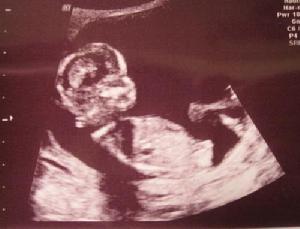

普通B超與三維B超區別

可以這樣理解,普通B超就像黑白照片,彩色B超就像彩色照片,而三維B超就像是攝像機所拍攝的VCR。普通B超和彩色B超看到的只是一個平面,而三維B超看到的是胎兒的立體圖像,胎兒的前後、左右、上下都可以看到,更加全面、真實且清晰。

舉例說明:比如兔唇,普通的B超看到的是一側裂開,而三維B超檢查出是上唇的左右兩邊各有一個裂開。再比如胎兒的手,如果胎兒的手掌是張開的,三維B超就可以清楚地看到每個指頭,但普通的B超是做不到的。還有就是血管方面的情況,二維的話只能看到一根血管的平面圖,而三維的話就可以看到血管伸進去的走向,看到血管壁。有關臍帶繞頸,三維B超可以清楚地看到繞了幾圈,繞得緊還是松。